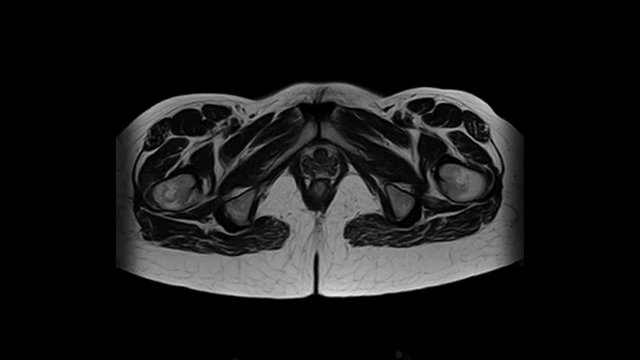

Der Retroperitonealraum oder einfach das Retroperitoneum (Spatium retroperitoneale) beinhaltet jene anatomischen Strukturen, die hinter dem Bauchfell (Peritoneum) liegen und nicht vom Bauchfell umschlossen werden. „Retroperitoneal“ bedeutet „hinter dem Peritoneum“.

Neben den retroperitonealen Organen befinden sich in der Medianebene des Retroperitonealraums die großen axialen Leitungsbahnen:

Da der Retroperitonealraum aus lockerem Bindegewebe und Fett besteht, erlaubt er ein Tumorwachstum von erheblicher Größe, bevor dieses auffällt. Deswegen werden Tumoren im Retroperitonealraum zufällig, oder oft erst sehr spät entdeckt, durch Obstruktion von Nerven oder Gefäßen, durch Metastasen oder seltener durch direkte Tumorinvasion. Retroperitoneale Malignome machen nur 1 % der Krebsarten des Bauchraums aus.